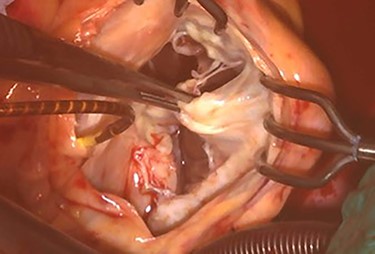

Intraoperative photograph; septal and posterior leaflet of tricuspid valve are severely damaged.

At his 1-year follow-up visit, the patient presented with shortness of breath on exertion and leg edema; thus, we decided to perform surgical correction. After median sternotomy, cardiopulmonary bypass was established with ascending aortic and bicaval venous cannulations. MyoPore (Greatbatch Medical, NY, USA) bipolar sutureless screw-in lead was attached to the left ventricle. A permanent PM was implanted, and left atrial appendage exclusion with AtriClip (AtriCure, OH, USA) was performed afterward. A right atriotomy was performed to facilitate exposure, wherein we found that the septal and posterior leaflets of the tricuspid valve were severely damaged (Fig. 3). Micra was placed over the right ventricular septum and was easily freed under direct vision (Fig. 4). After the leaflets were excised, an Epic (St Jude Medical, MN, USA) 33-mm bioprosthesis was implanted.